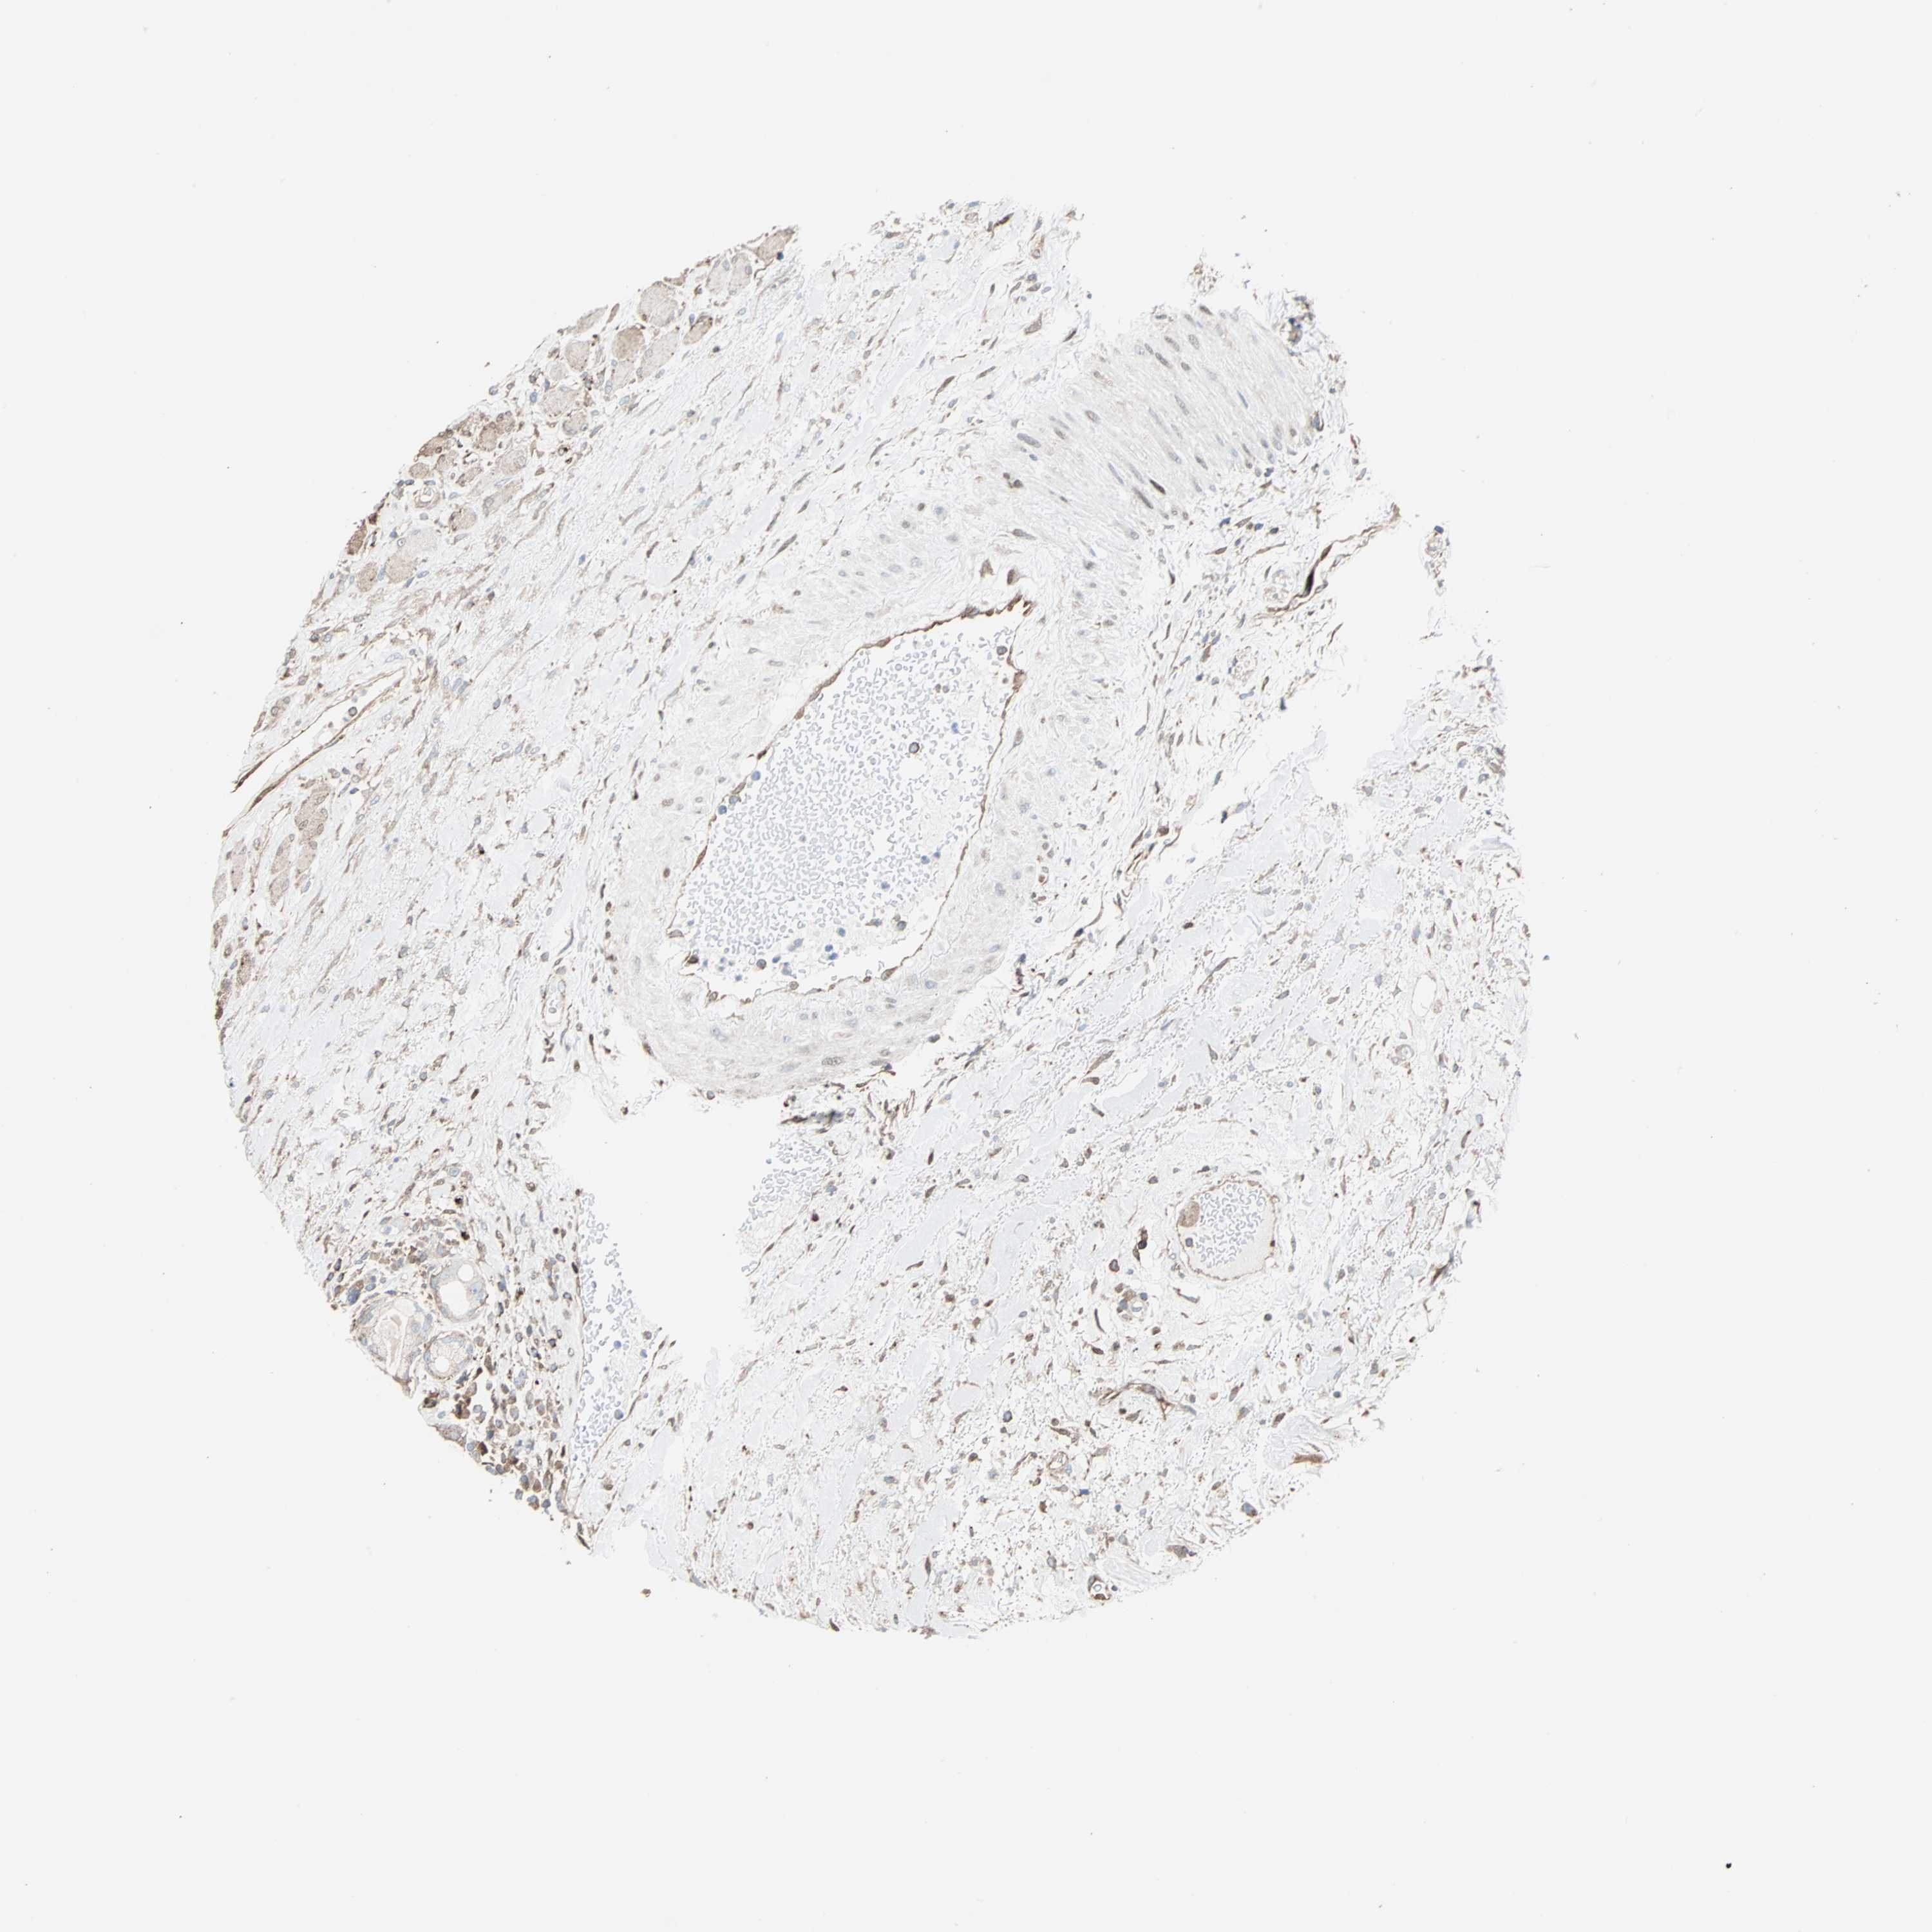

HEAD AND NECK CANCER - Protein expressioni

A mouse-over function shows sample information and annotation data. Click on an image to view it in a full screen mode. Samples can be filtered based on level of antibody staining by selecting one or several of the following categories: high, medium, low and not detected. The assay and annotation is described here.

Antibody stainingi

Antibody staining in the annotated cell types in the current human tissue is reported as not detected, low, medium, or high, based on conventional immunohistochemistry profiling in selected tissues. This score is based on the combination of the staining intensity and fraction of stained cells.

Each image is clickable and will lead to virtual microscopy that enables deeper exploration of all samples and also displays staining intensity scores, fraction scores and subcellular localization as well as patient and tissue information for each sample.

Antibody CAB004264

Antibody CAB005030

Staining

High

Medium

Low

Not detected

Intensity

Strong

Moderate

Weak

Negative

Quantity

>75%

75%-25%

<25%

None

Location

Nuclear

Cytoplasmic/membranous

Cytoplasmic/membranous,nuclear

Squamous cell carcinoma, NOS

Adenocarcinoma, NOS

Adenoma, NOS